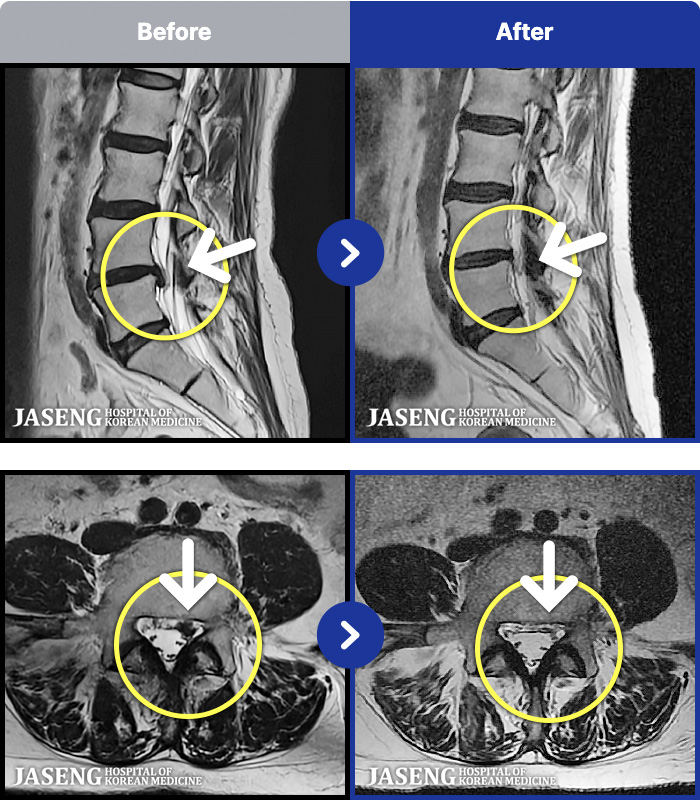

MRI ġ

54 MRI ũ ʸ Ȯϼ.

[_㸮ũ] кο ٸ ٸ ٷϷ Ÿ.